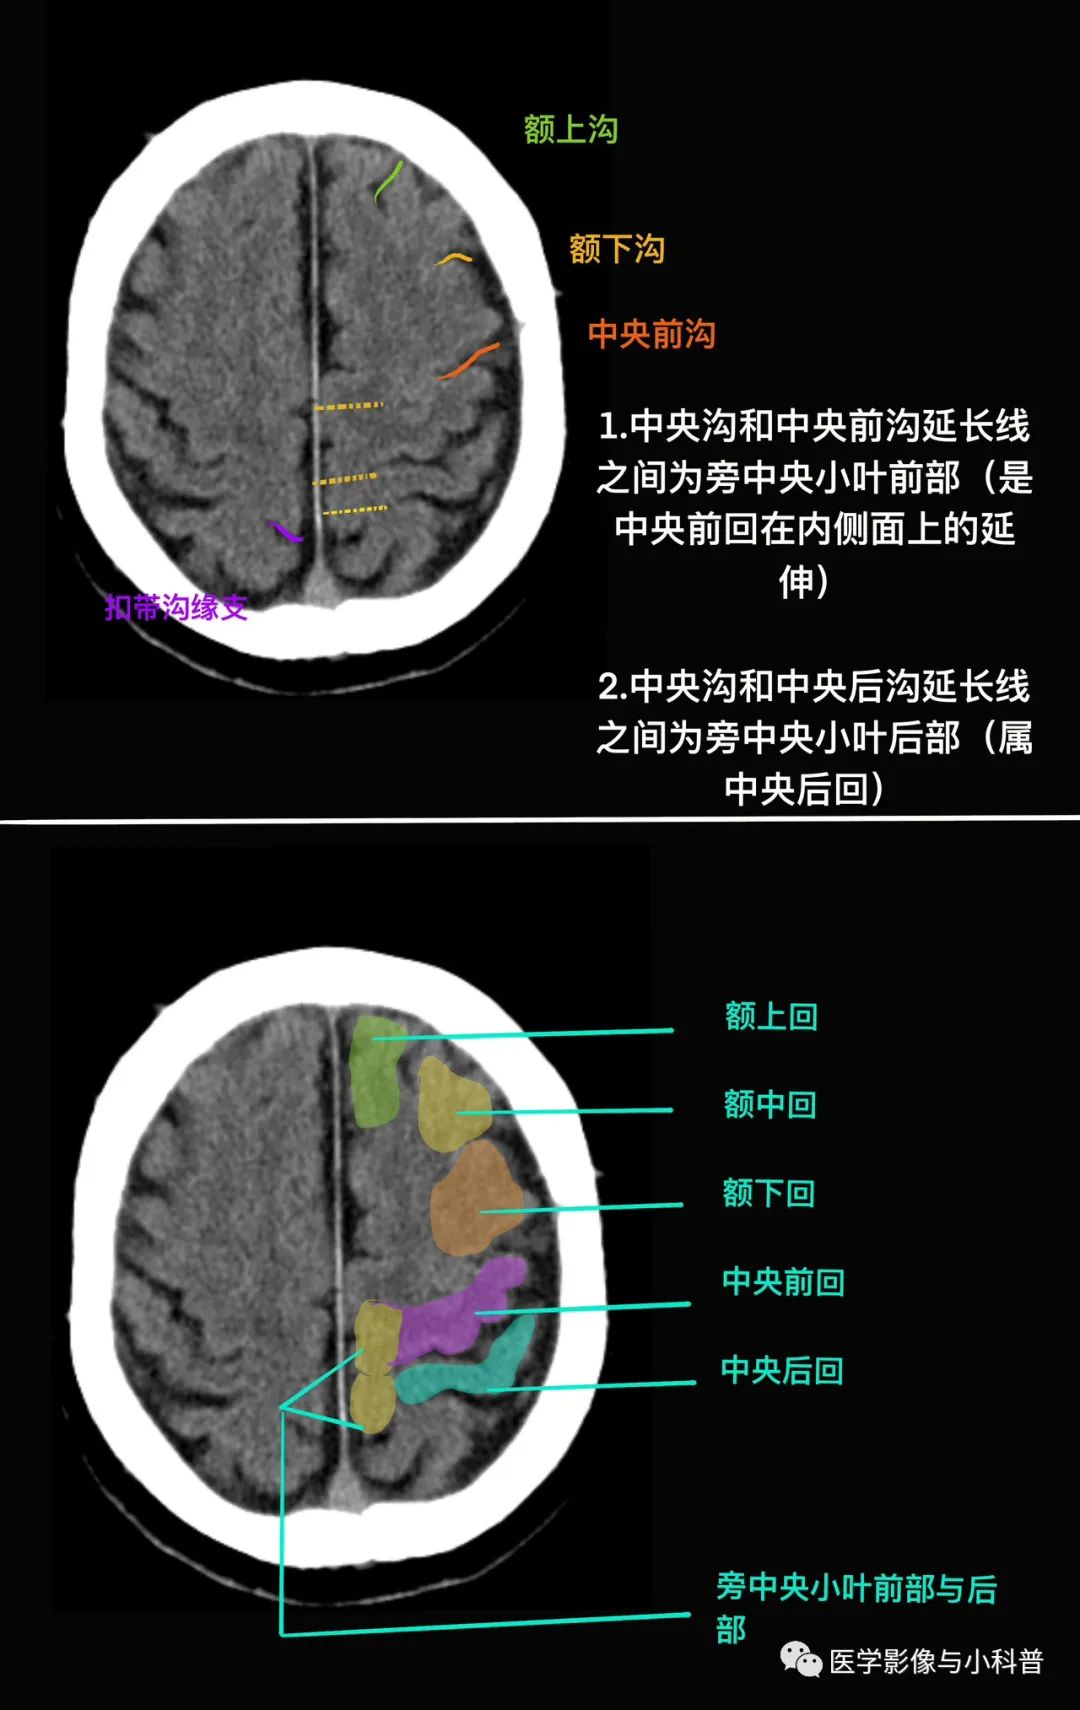

1. 第一步:先找中央沟,中央沟前为额叶,后为顶叶

第一步:先找中央沟,中央沟前为额叶,后为顶叶

中央沟 端脑背外侧面的主要沟 外侧沟 中央前沟 中央后沟 额上沟 额下